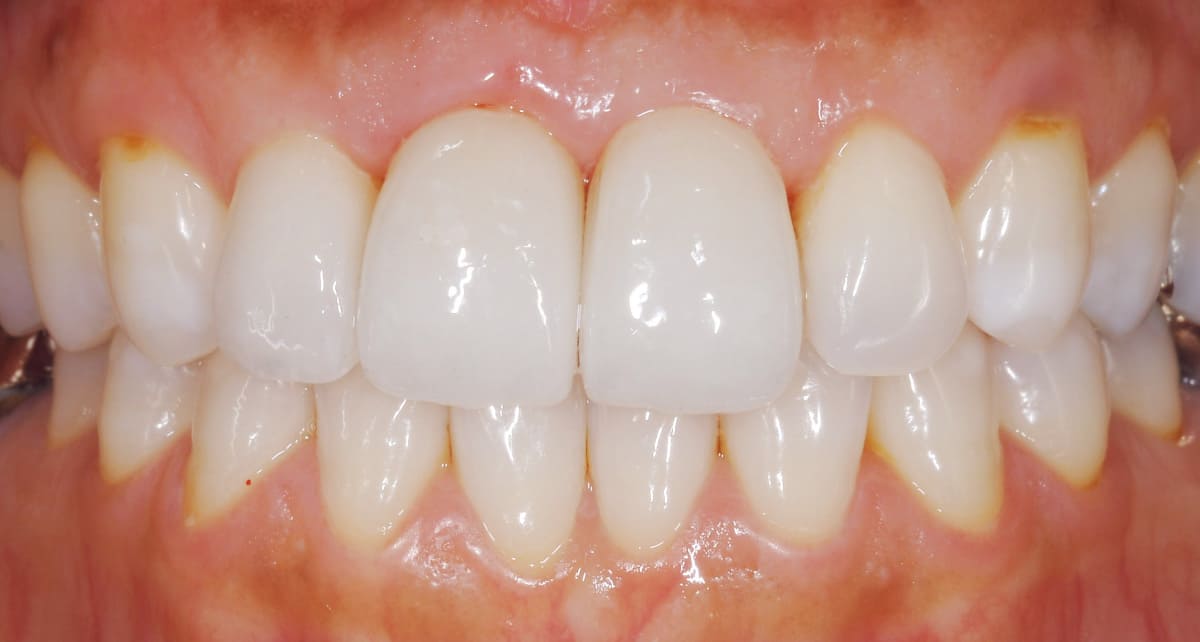

セラミック|費用はかかるが仕上がりの良さは抜群。

Before

After

よりきれいな仕上がりを目指すのであれば、やはりセラミックがファーストチョイス。透明感があり、自然歯と変わらない白さが望めるからだ。ジルコニアよりコストがかかるので、前歯はセラミック、奥歯はジルコニアという選択も。

【料金】15万円〜

【治療期間】1週間〜3週間程度

(特別な機材がある病院ではワンデイ治療が可能)